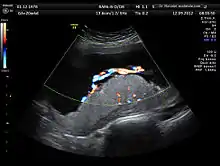

A 3D Power Doppler image of vasculature in 20-week placenta